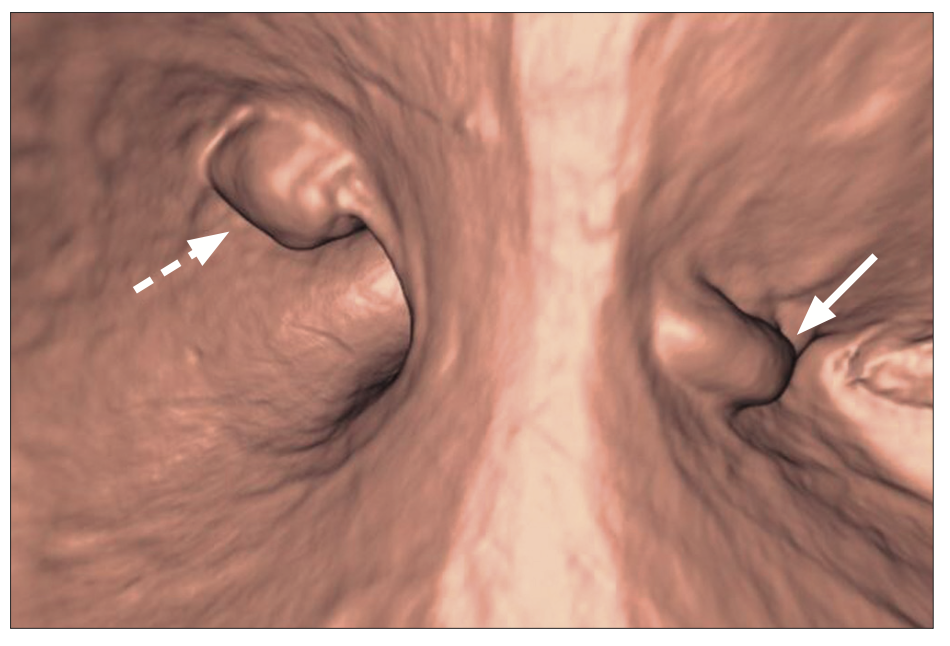

La tomografía computada prequirúrgica evidenció una masa subcardial con crecimiento hacia la luz y realce homogéneo tras la administración de contraste, y otra masa en el cuerpo distal de crecimiento mixto y realce heterogéneo (Figuras 1A y 1B). La reconstrucción tridimensional, similar a un estudio baritado del estómago, facilitó la localización precisa de ambos tumores (Figura 2). La endoscopía virtual proporcionó una visión intraluminal de ambas lesiones; mostrando la mucosa gástrica preservada (Figura 3). No se evidenciaron adenopatías regionales ni metástasis a distancia.

Figura 3.